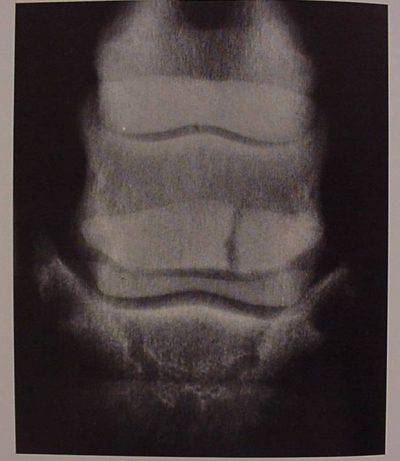

navicolite-4La malattia navicolare o Navicolite del cavallo è una malattia cronica degli arti anteriori associata a dolore che origina dal sesamoide distale (osso navicolare). Di rilievo comune in associazione alle lesioni dell’osso sono fibrillazioni della faccia dorsale del tendine FPD, con o senza aderenze osso-tendine. A differenza della Laminite non è caratterizzata da sintomatologia sistemica ed il decorso è generalmente subacuto o cronico. Vi possono essere anche lesioni (alterazioni) di altri componenti del Complesso o Apparato navicolare come: